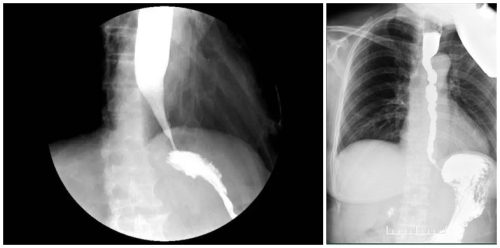

4月17日,患者严阿姨因“反复进食后呕吐二年,加重一周”前来我院就诊。胃镜检查提示患者贲门失弛缓,食道钡餐提示贲门失弛缓。经消化内科医疗团队讨论,诊断为贲门失弛缓症。

4月21日,内科主任兼消化内科主任杨晓军及医疗团队在麻醉科的配合下,为患者实施了无痛胃镜下经口肌层切开手术(POEM)。通过微创手术松弛食道下括约肌,加快了食道排空,从而消除了食道扩张及食物潴留,改善了进食梗阻,手术大获成功。术后第二天,患者喝了米汤而无梗阻感;术后第三天,又很顺畅的吃了烂面条……每天,患者的进食量不断加大,不再呕吐。

据消化内科杨晓军主任介绍,贲门失弛缓是因食管蠕动减低,食管下括约肌的功能减弱,食管和胃之间的通道不能完全开放,导致食物在食管底部积存、滞留。贲门失弛缓分经典型失弛缓和痉挛性失弛缓。当前,我院开展的无痛胃镜下经口肌层切开手术(POEM)是采用隧道技术、肌切开术,是目前开展高难度、高疗效的新技术。手术所需时间较短,患者耐受性好,是解决贲门失弛缓的微创方式。通过此方法可有效减轻患者的症状,改善其生活质量。医院自2019年开展POEM手术以来,成功开展此类手术3台,取得了良好的疗效。